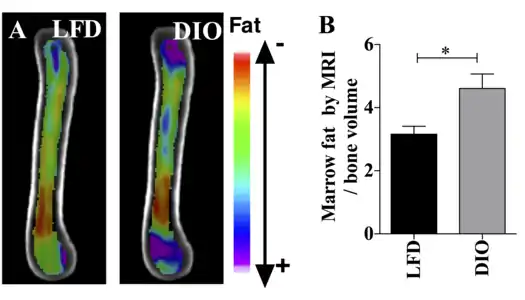

This figure demonstrates the use of the osmium- μCT method with advanced image processing to quantify BMAT. In this figure, running exercise is shown to suppress BMAT despite PPARγ agonist. Fat binder osmium is imaged via μCT (A ) in n =5 per group overlaid images. Quantification of osmium as BMAT/ bone volume in the whole femur is shown. a, significant due to Rosi. b, significant due to exercise. Rosi=rosiglizaone, CTL=control, E=exercise. This figure demonstrates the use of MRI imaging (9.4T scanner) along with advanced image processing to quantify BMAT. The images and graph demonstrate that BMAT is higher in obese compared with lean mice. B6 mice were fed HFD from age 4 wk until age 16 wk. BMAT was quantified by MRI. A) n=10 superimposed group average images are shown B) BMAT normalized to bone volume in each group.

This figure demonstrates the use of MRI imaging (9.4T scanner) along with advanced image processing to quantify BMAT. The images and graph demonstrate that BMAT is higher in obese compared with lean mice. B6 mice were fed HFD from age 4 wk until age 16 wk. BMAT was quantified by MRI. A) n=10 superimposed group average images are shown B) BMAT normalized to bone volume in each group._.jpg.webp) Representative distal femur histologic section of a 16-week-old healthy C57BL/6 mouse demonstrating a typical quantity of marrow adipocytes.